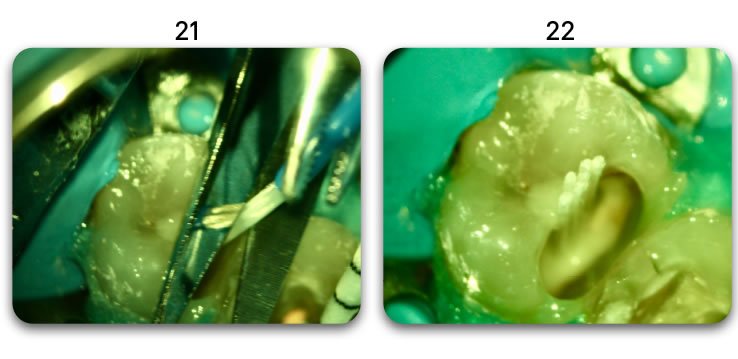

Template for x-rays